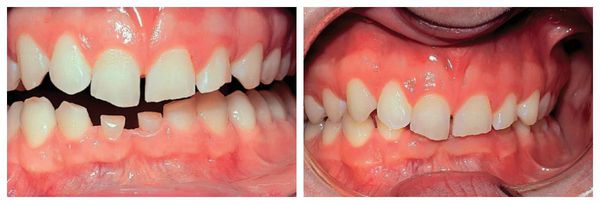

Niedopasowanie rozmiaru zębów do wielkości i kształtu szczęki może prowadzić do licznych zaburzeń okluzyjnych, czyli wad zgryzu (anomalii zgryzowych). Zarówno mikrodoncja (microdentia), jak i makrodoncja (macrodontia) powodują nieprawidłowe rozmieszczenie zębów w łuku zębowym i zaburzają równowagę między szczęką a żuchwą.

Najczęstsze konsekwencje to:

• Przerwy między zębami – powstawanie odstępów między siekaczami przyśrodkowymi (diastema) lub pomiędzy innymi zębami (tremy);

• Stłoczenie zębów (stłoczenie łuku zębowego) – zbyt mała przestrzeń w łuku zębowym powoduje, że zęby zachodzą na siebie, obracają się lub wyrastają pod niewłaściwym kątem;

• Przemieszczenie zębów (dislocatio dentis) – przesunięcie zębów z prawidłowego ustawienia w wyniku ograniczonej przestrzeni lub asymetrii wzrostu szczęk;

• Obrót zębów wokół własnej osi (tortoanomalie) – skręcenie korony i korzenia, najczęściej w obrębie siekaczy i kłów;

• Nieprawidłowy zgryz (malokluzja) – zaburzony kontakt między łukami zębowymi prowadzący do problemów z żuciem, wymową, a także do nadmiernego ścierania się zębów.

Tego rodzaju zaburzenia wymagają leczenia ortodontycznego, a w niektórych przypadkach także korekty protetycznej, aby przywrócić prawidłową funkcję żucia i estetykę uśmiechu.

Głęboki zgryz na tle mikrodoncji